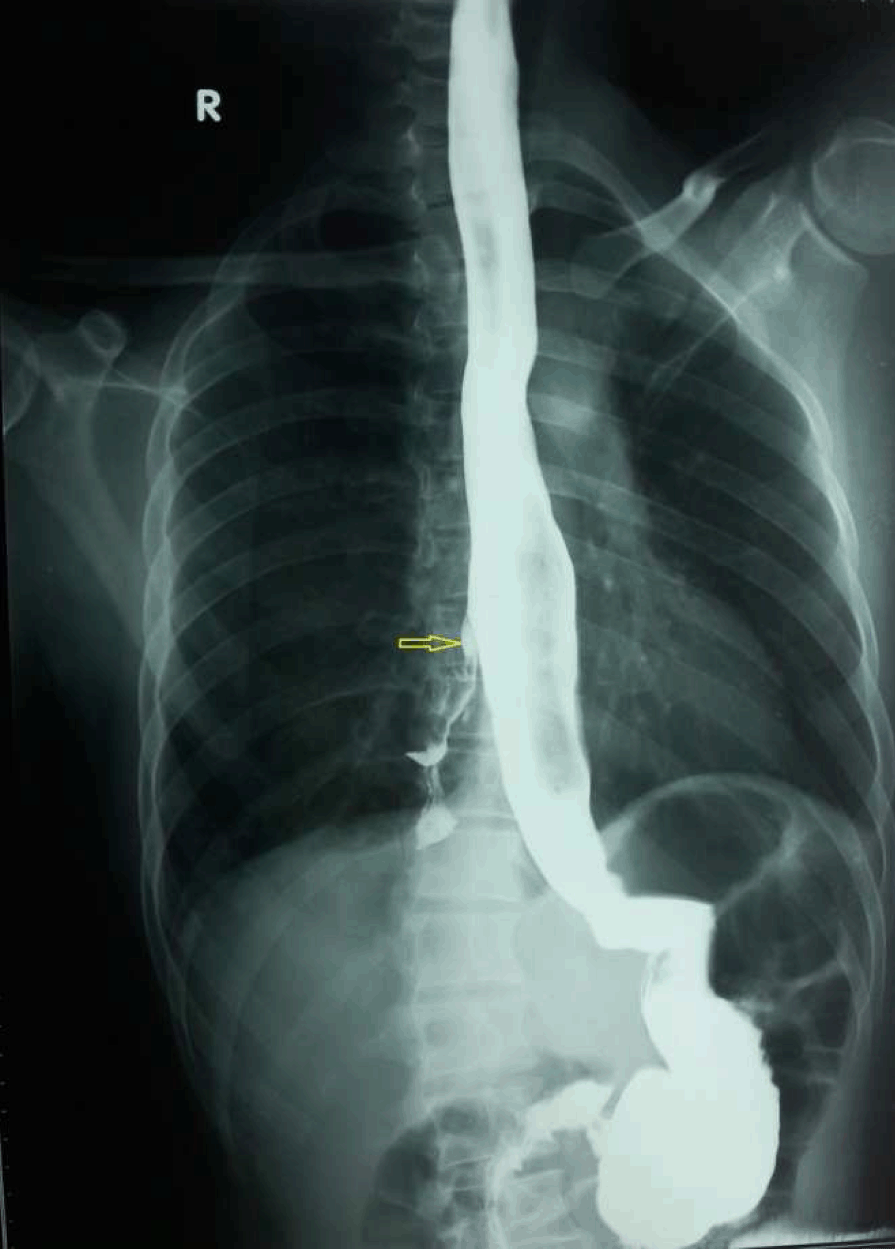

A 37-year-old male presented to our department with history of cough with expectoration immediately after taking food, especially liquids for last 13 years. He had two bouts of hemoptysis in the last 15 days which had made him seek medical attention. Clinically, chest on auscultation had crackles in right infra-scapular region. Chest X-ray revealed patchy opacities in the right lower zone paracardiac region. Computed tomography (CT) scan of thorax revealed consolidation in posterior segment of the right lower lobe with no evidence of lung sequestration or cyst. Upper gastrointestinal endoscopy showed a fistulous opening in the mid esophagus 32 cm from the incisor teeth. It did not show any evidence of malignancy, granulomatous disease or any other acquired basis for the fistula. Simultaneously, methylene blue was injected into the fistulous tract and bronchoscopy was done which was normal. Barium swallow showed fistulous communication between mid esophagus and right lower lobe bronchus at lower border of T7 with barium passing downward into the right lung (Figure 1).

Preoperative evaluation done included pulmonary function tests, echocardiogram and electrocardiogram. Incentive spirometry was started for better postoperative outcome. Preoperatively, 1 fr size guide wire was introduced endoscopically into the fistulous tract to aid identification of fistula. Patient underwent right posterolateral thoracotomy. There were minimal adhesions around the fistulous site which was identified about 5 cm below the level of entry of azygos vein into superior vena cava. Azygos vein was isolated, ligated and cut to aid esophagus to be encircled, to localize the fistulous tract. As the guide wire was not palpable through the tract, intraoperative endoscopy was done and fistula tract location was confirmed. The fistulous tract was dissected, it was 10 mm long. The tract was excised, both the esophageal and bronchial ends were healthy and were closed with 4–0 Vicryl. An intraoperative leak test was done using endoscopy which confirmed the integrity of the repair and an intercostal drain placed (Figure 2) (Figure 3) (Figure 4).

Figure 1: Barium esophagogram showing esophagobronchial fistula between the middle third of the esophagus and the right lower bronchus with downward passage of barium (shown with arrow).